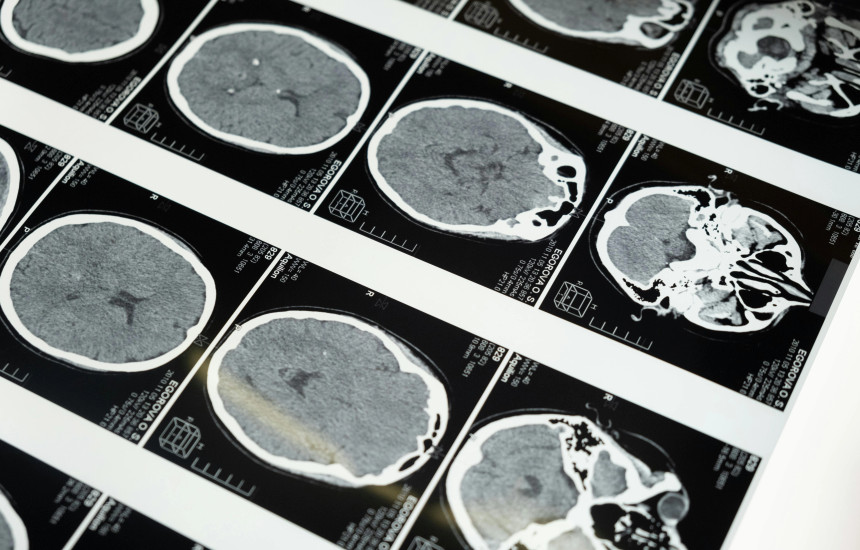

Në një studim të ri, të botuar në revistën Nature Neuroscience, teknologjia u testua te një grua 47-vjeçare me paralizë të katër gjymtyrëve, e cila nuk kishte folur për 18 vjet pas një sulmi në tru. Pajisja iu implantua në tru gjatë një operacioni klinik dhe lejonte përkthimin e synimit për të folur në fjali të rrjedhshme.

Implanti është vendosur mbi qendrën e të folurit në tru dhe dërgon fragmente të vogla tingujsh çdo 80 milisekonda, afërsisht gjysmë rrokjeje, për t’u shndërruar në fjalë.